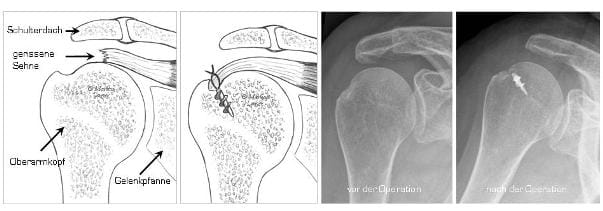

ROTATORENMANSCHETTENNAHT

Die Schemazeichnung links zeigt wie ein Sehnenriss genäht werden kann rechts sieht man die Röntgenkontrolle nach einer Sehnennaht mit einem Nahtanker

Die Schemazeichnung links zeigt, wie ein Sehnenriss genäht werden kann. Rechts sieht man die Röntgenkontrolle nach einer Sehnennaht mit einem Nahtanker. (Bilder: Orthopädie)